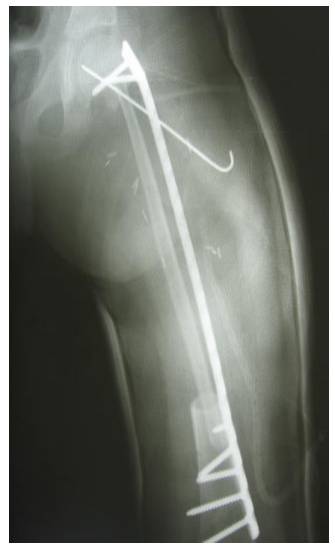

Proksimal femur yerleşimli Ewing sarkoma bağlı patolojik kırık nedeniyle kemoterapiyi takiben geniş rezeksiyon ve vaskülerize fibula ile rekonstrüksiyon yapılan kız çocuğu hastamız

Ameliyat Sonrası: Röntgende çıkarılan tümörlü kemiğin yerine uygulanan vaskülerize fibulanın plak ve K teli ile fiksasyonu görülmekte